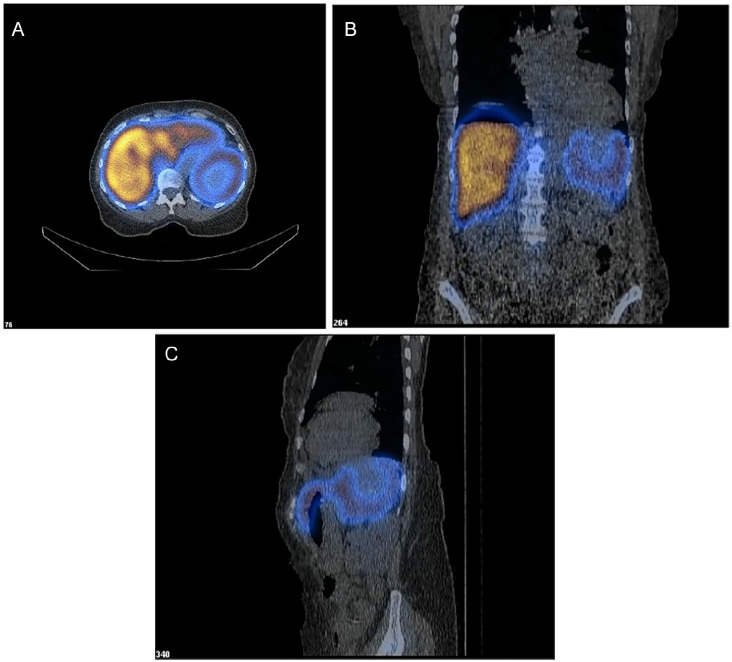

Littoral cell angioma (LCA) is a rare primary splenic vascular neoplasm originating from the littoral cells of the reticuloendothelial system. Splenectomy is the accepted mode of definitive diagnosis and treatment. With fewer than 200 reported cases, LCA remains poorly understood. Herein, we provide an enhanced insight into its histology and highlight the role of nuclear imaging in aiding LCA diagnosis. A 63-year-old female with a history of stage II multiple myeloma (MM) and rheumatoid arthritis was incidentally found to have a slowly enlarging splenic mass over a 6-year period. Given her candidacy for autologous hematopoietic stem cell transplantation for MM, further evaluation of the splenic lesion was pursued using nuclear medicine (NM) liver-spleen scan, which revealed a photopenic region consistent with a benign hemorrhagic mass. Subsequent splenectomy and histopathological analysis confirmed the diagnosis of LCA, with immunohistochemistry demonstrating CD68+ and CD31+ expression, highlighting LCA's unique dual histiocytic and endothelial character. This case highlights the diagnostic challenge posed by LCA due to its nonspecific clinical presentation and imaging findings. While splenectomy remains the gold standard for diagnosis, our findings suggest that NM liver-spleen scan imaging may aid in differentiating LCA from malignant splenic masses preoperatively. Furthermore, this case reinforces the association between LCA and hematologic malignancies, supporting the hypothesis that immune dysregulation may play a role in its pathogenesis. This underscores the importance of considering LCA in the differential diagnosis of splenic masses, particularly in cases involving a history of malignancy and/or immune system abnormalities.